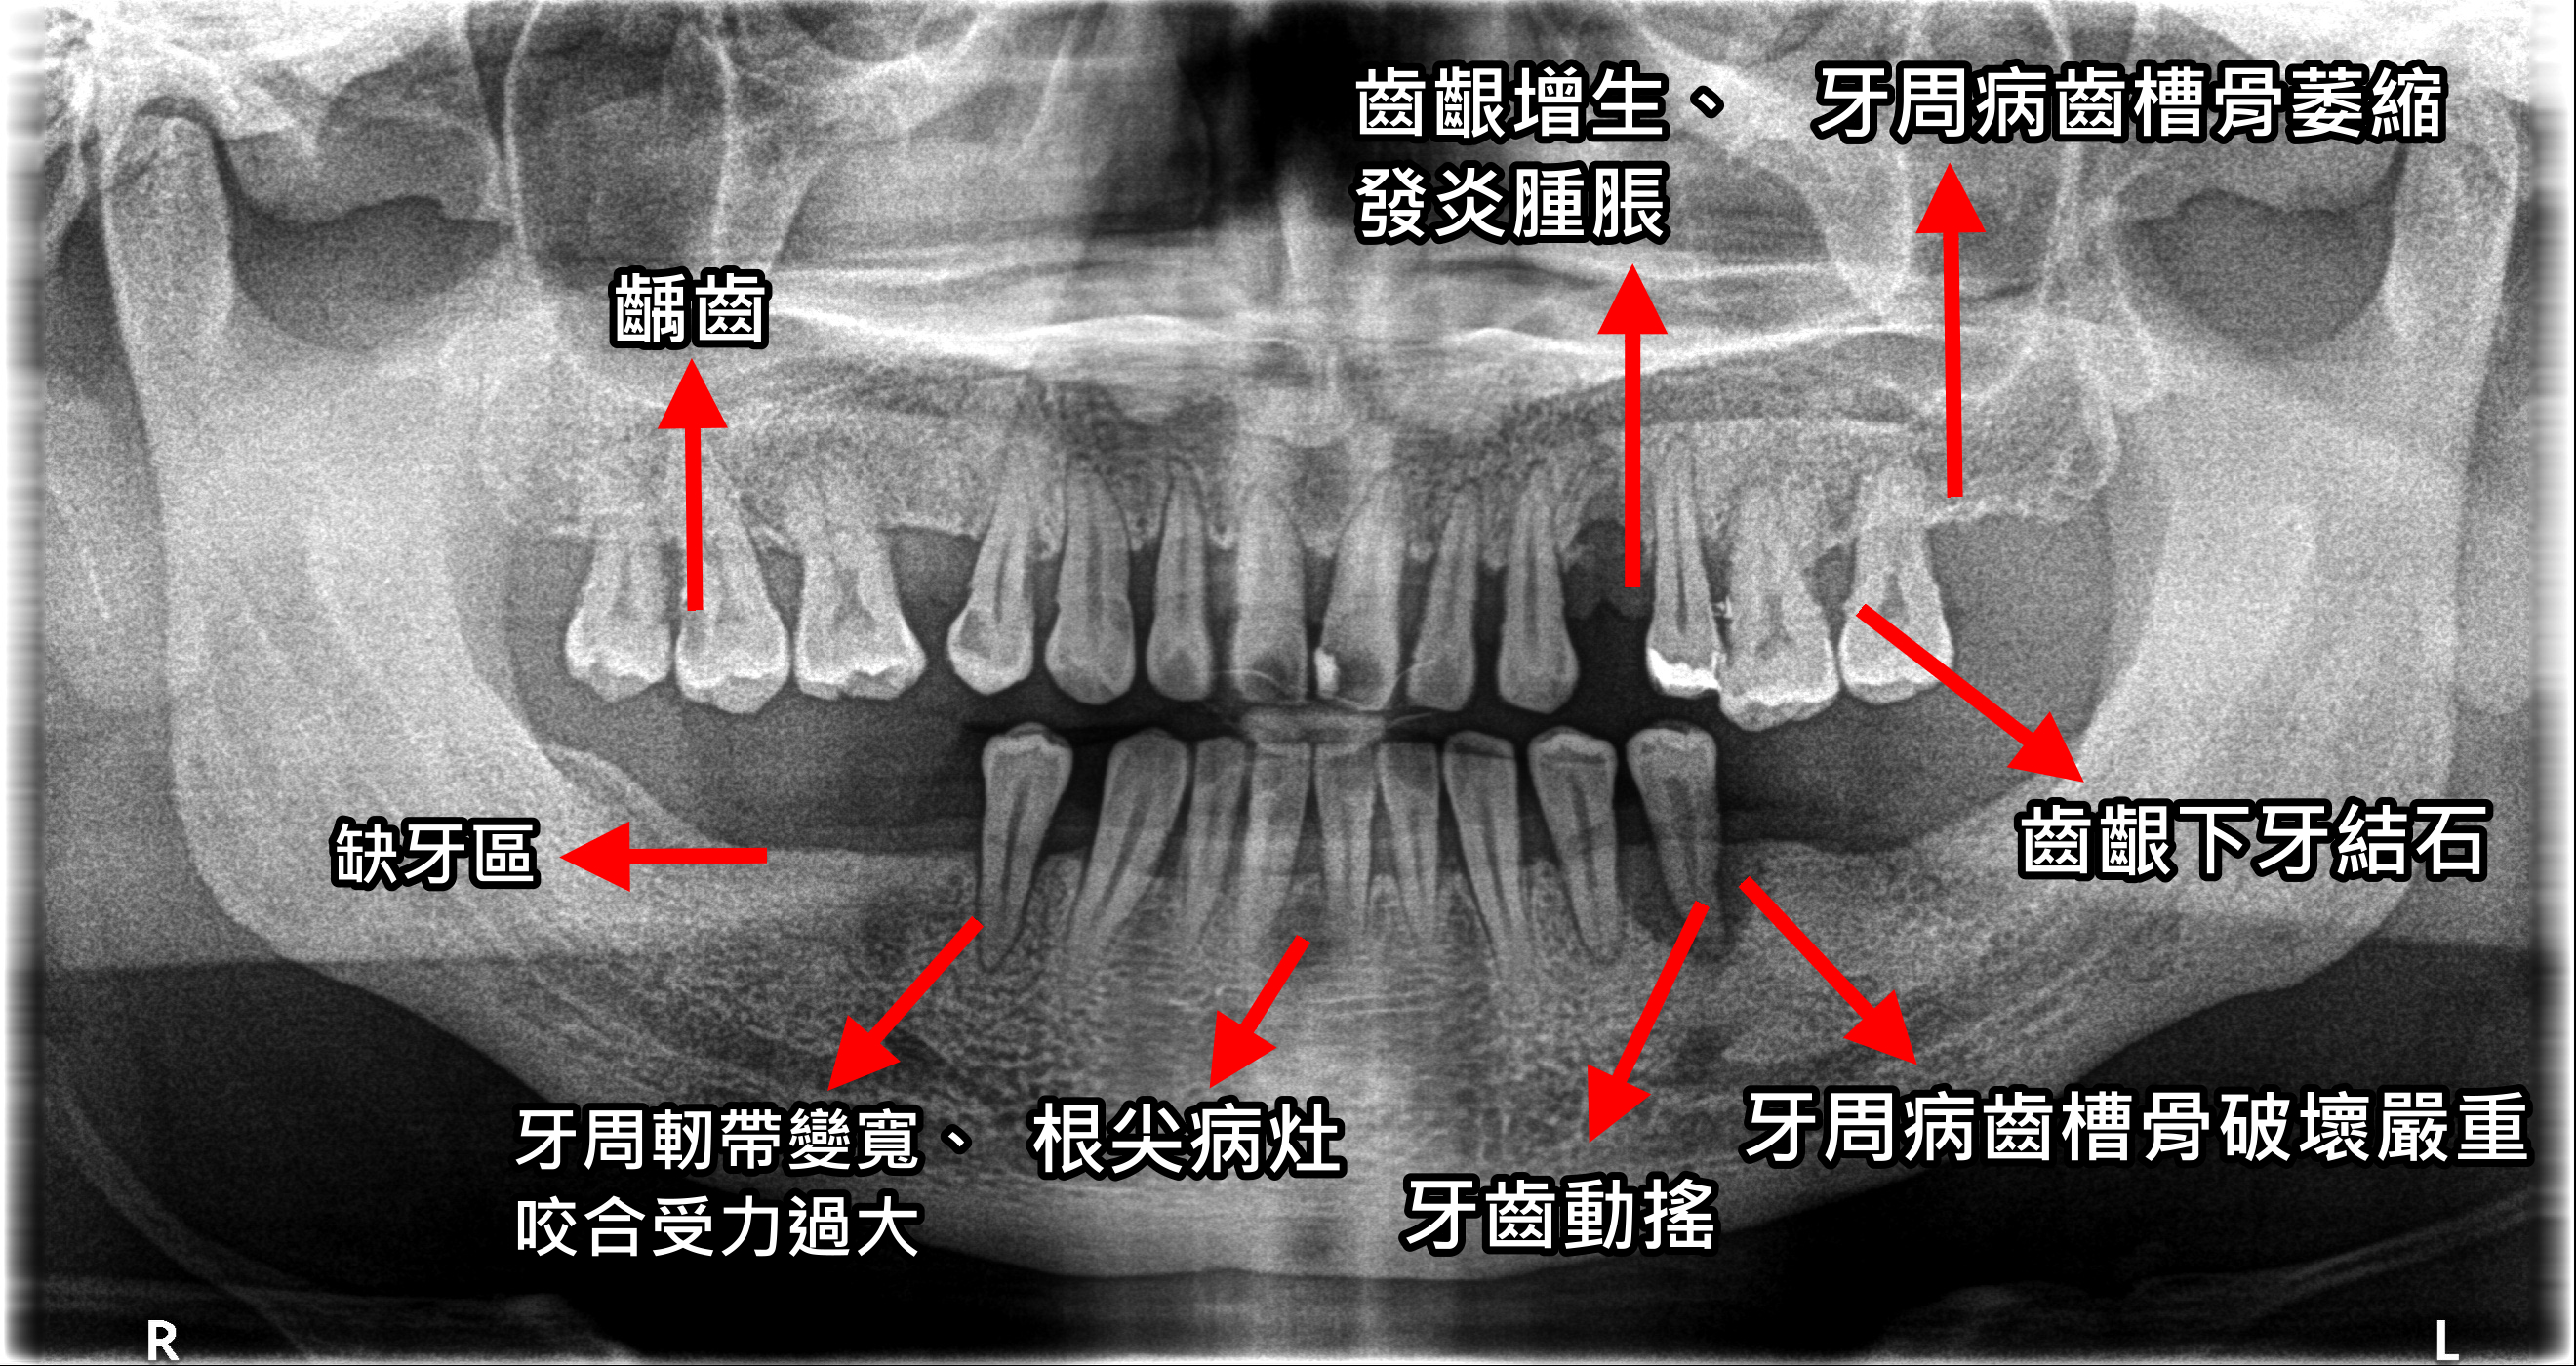

動搖 意思

» 齒 牙 動搖 意思 (99) 사진

齒 牙 動搖 意思 (99) 사진